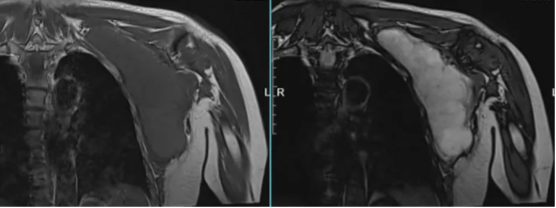

图示:MRI增强,左肩部及侧胸壁囊实性肿块。T1WI呈等信号,T2WI呈高信号